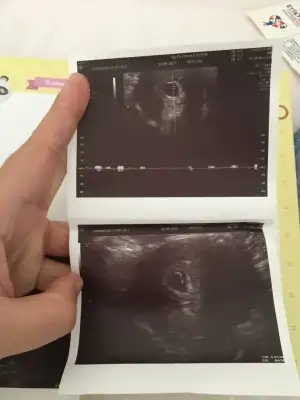

Cinsiyet tahmini sen anlayanlar bakabilir mi

ErkekBanada bir tahminde bulunur musunuz rica etsem çok merak ediyorum 9 +4 haftalık burda

Eminsiniz neye göre yorumladiniz

Ultrason konumuna göre ama emin değilim tabiki haber verirsen sevinirimEminsiniz neye göre yorumladiniz

Doktorda %80 erkek dedi ama kesin birşey söylemedi bakalım artık bizde çok merak ediyoruz hayırlısı olsun inşallahUltrason konumuna göre ama emin değilim tabiki haber verirsen sevinirim

dün öğrendim kızBebek henuz yeni olusmus ama keseye ve yerlesime göre kiz

Bizde erkek çok istiyoruz bakar mısın tahmin nedir lütfenKese ve yerlesim erkege benziyor hayirlisi olsun

Canım Banada tahmin de bulunur musun erkek çok istiyoruzBence de benim de oyleydi erkek

Bende ultrason fotoğrafımı atsam tahminde bulunur musunuzDaha cok kucuk ama illa bi tahminde buluncaksam erkek derim

Erkege benziyor 11-12 haftada daha net oluyor yine gonderirseniz bakarimBizde erkek çok istiyoruz bakar mısın tahmin nedir lütfen